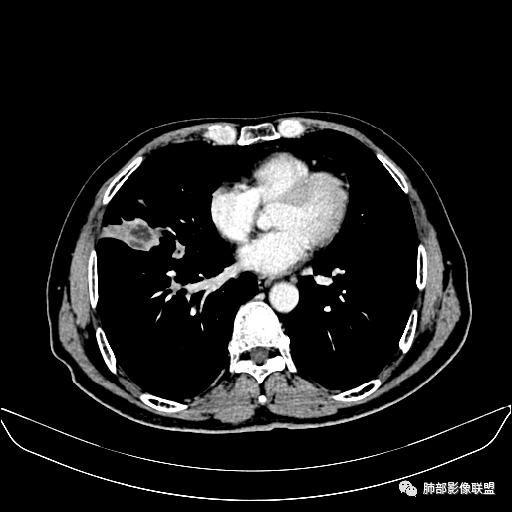

住院4天后行胸部增强CT

动脉期

老年男性,因“咳嗽咳痰1月余。”入院。病程中咳嗽咳痰,咳黄白痰,间断咯少许鲜红色痰血。PPD阳性。胸CT:右肺中叶外侧段支气管管腔阻塞,大片实性病变,病灶边缘光滑,部分边缘膨隆,可见分叶,肺门及纵隔可见肿大淋巴结,并可见钙化。增强可见病灶明显强化,而且延迟强化明显,病灶内多发低密度区,内见血管影,血管变细、部分血管破坏。考虑恶性病变可能性大,鉴别慢性肉芽肿性病变。

右肺中叶外侧段管腔阻塞、实性病变,病灶边缘光滑,可见分叶,肺门及纵隔可见肿大淋巴结,并可见钙化。增强可见病灶内多发低密度区。

考虑肉芽肿性炎可能。

TB  放线  奴卡 NTM

老年男性,咳嗽、咳痰1月余,间断血痰。PPD阳性。

胸CT:跨叶大肿块,主体在中叶,右中叶外侧段支气管阻塞,病灶部分边缘膨隆,可见分叶,部分边缘平直,肺门及纵隔可见肿大淋巴结。增强病灶不均匀强化,延迟强化明显,病灶内多发低密度区,内见血管飘浮,部分血管变细、模糊。考虑:恶性病变可能性大,大细胞?淋巴瘤?鉴别慢性肉芽肿性病变。